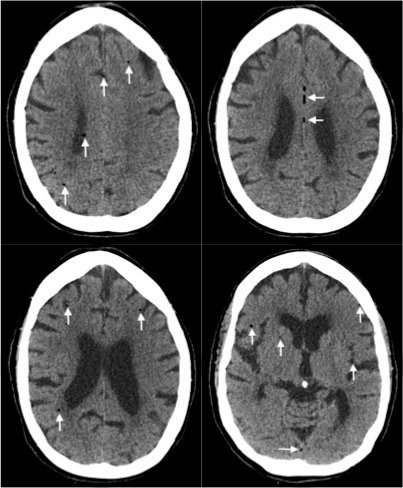

Non-contrast head computed tomography (CT) demonstrates multifocal bilateral hypodense lesions (white arrows) representing air emboli. Note the lesions are located in the intra-axial distribution which indicates an underlying vascular origin.

This event can arise in clinical and non-clinical settings and the diagnosis of cerebral air embolism should begin with clinical suspicion and evaluation. Most common causes include thoracentesis, hemodialysis, angiography, tissue biopsy, scuba diving, and central line or other vascular access procedures. Clinical signs of air embolism are broad depending on the affected system and include altered mental status, focal neurologic deficits in the distribution of the affected neurological region, cyanosis, hypoxia, hypercapnia, hypotension, wheezing, and bronchospasm.4 Recommended diagnostic imaging for cerebral air imaging includes CT and magnetic resonance imaging (MRI), but CT is most often performed first due to availability and the short duration of the test.5 The location of intracranial air emboli can be found in the intra-axial or extra-axial distribution and may indicate the possible etiology. Pneumocephalus is usually found in the extra-axial space most commonly after trauma or neurosurgery while air emboli are found in the intra-axial vascular distribution.6